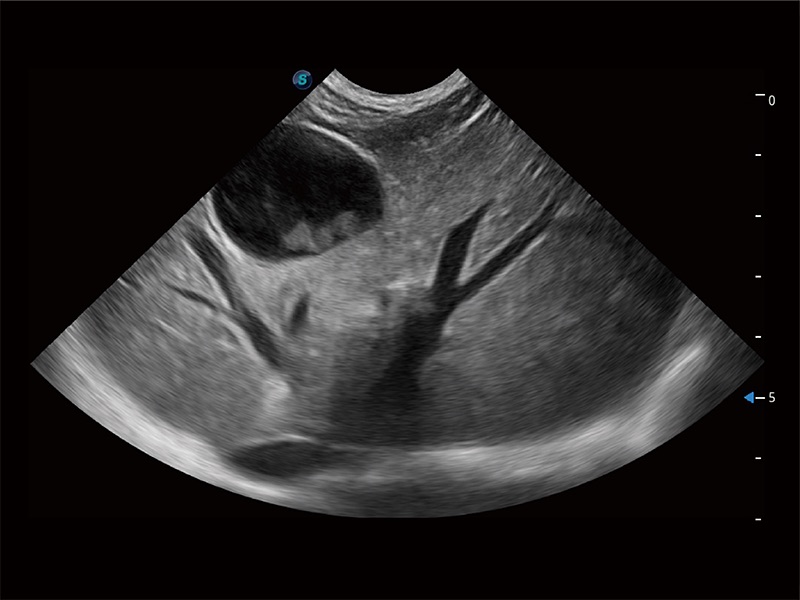

(犬)肝脏

(犬)肠道